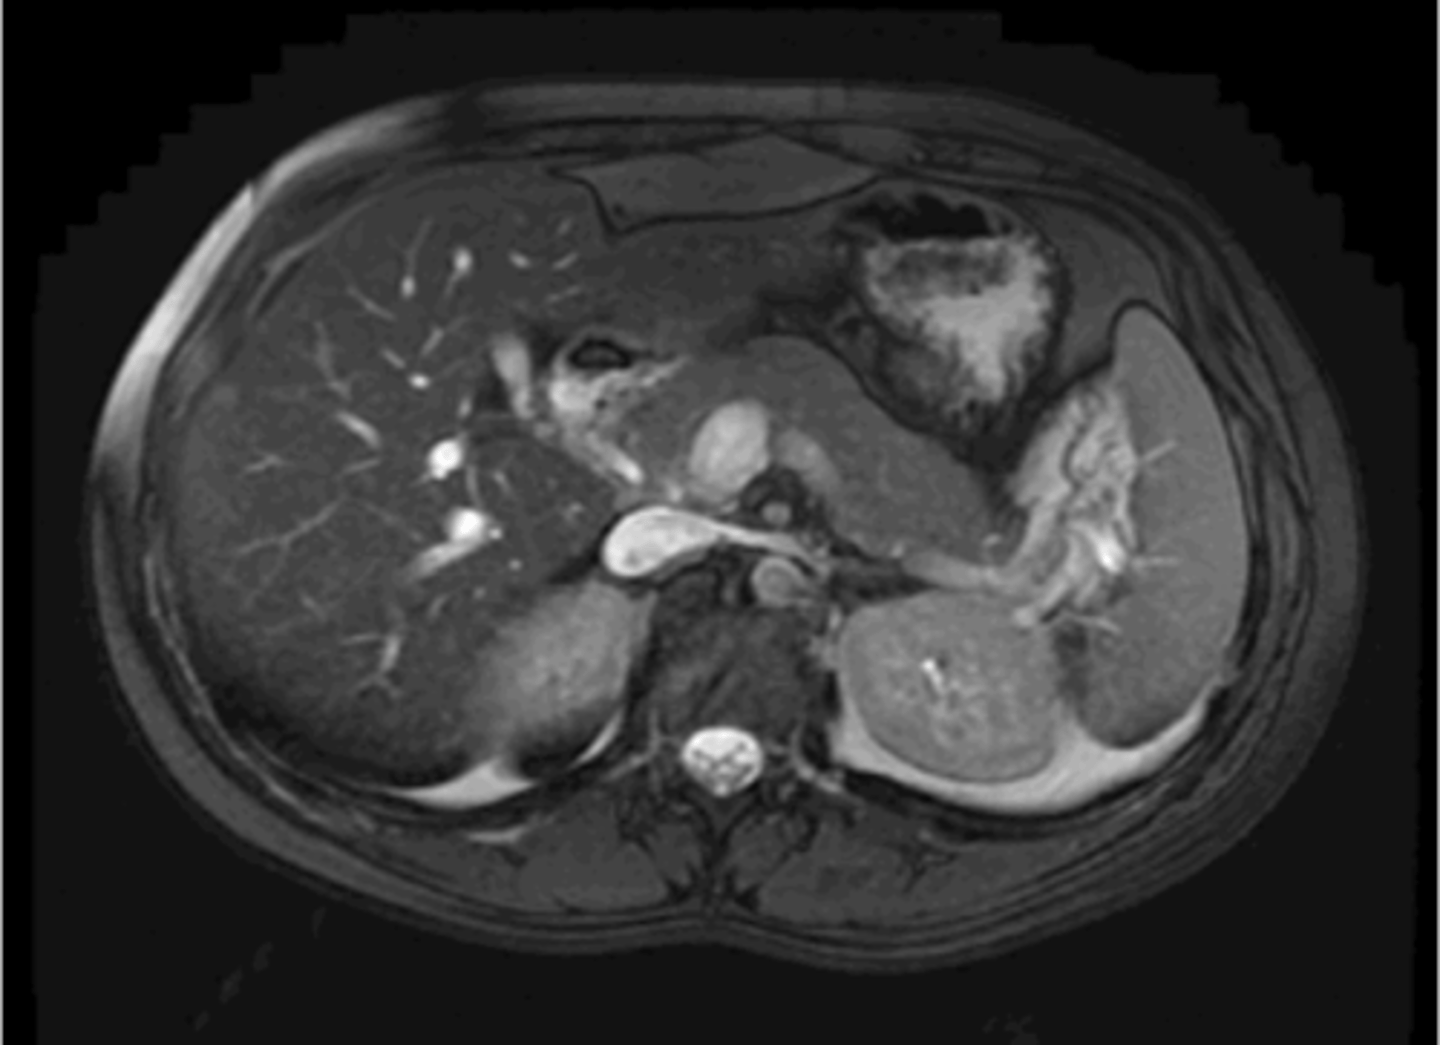

Normal pancreas MRI

Normal CT